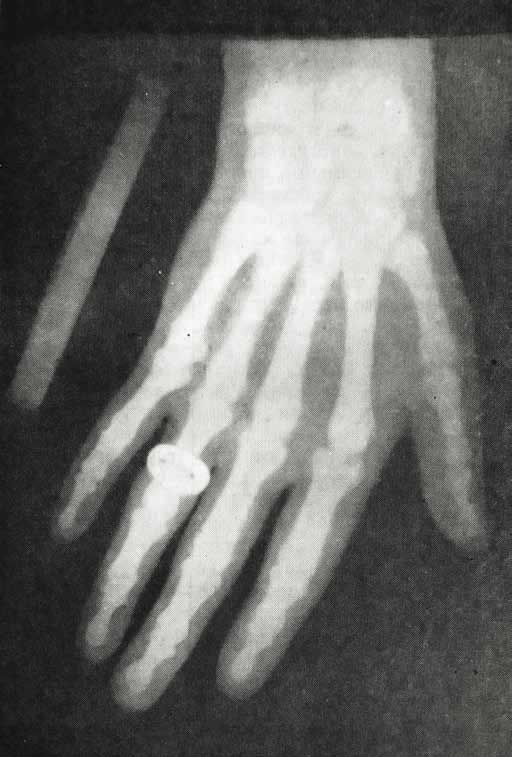

Рентгеновский снимок руки А. С. Попова. 1896 г. (Центральный музей связи имени А. С. Попова.)